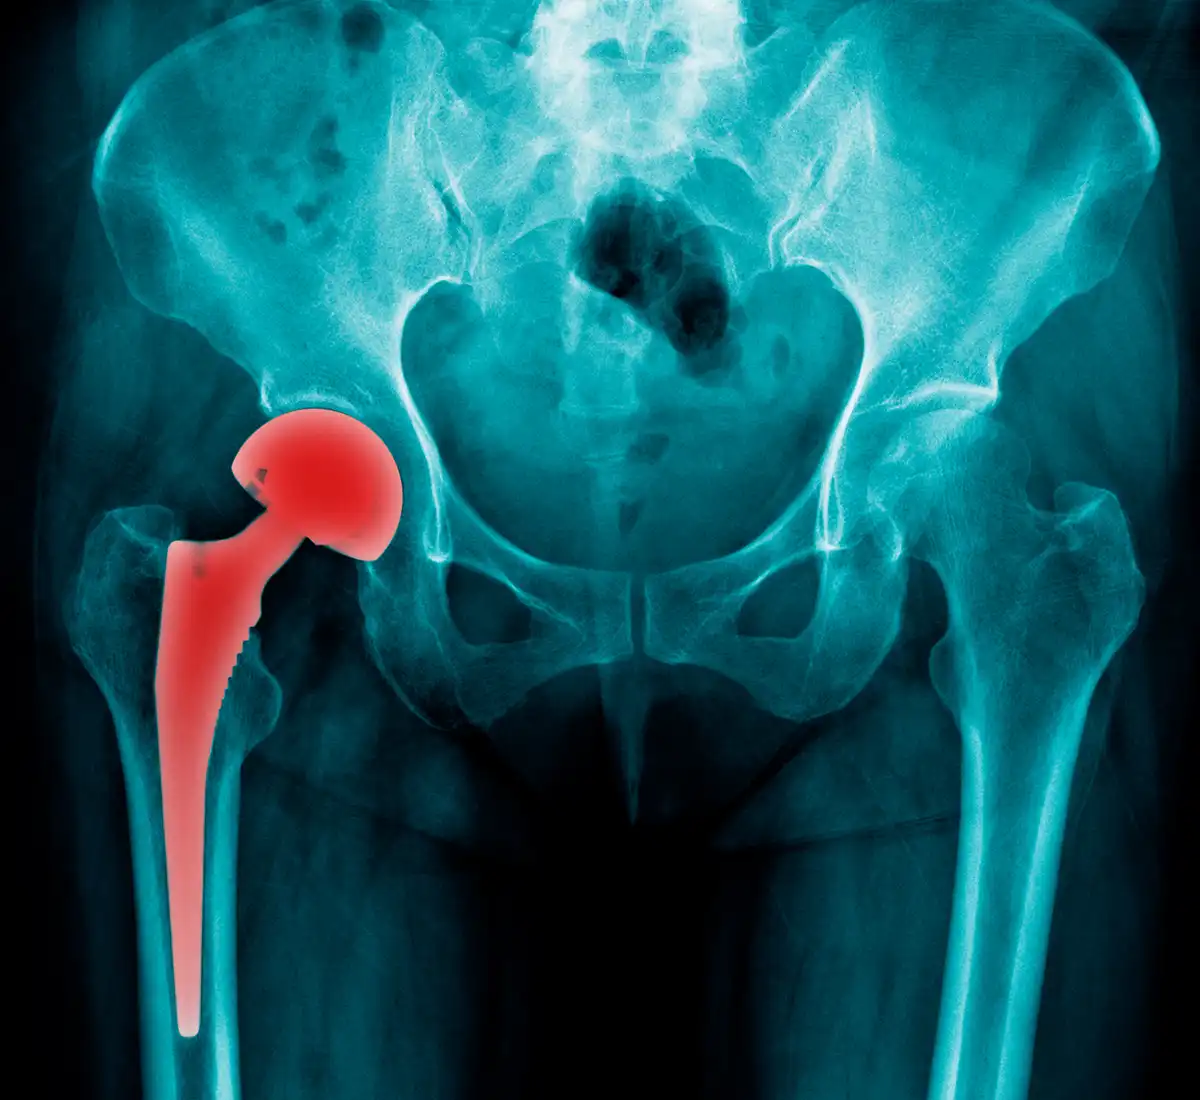

The hip joint is one of the most important parts of our body. This joint can move into three joints. It is known for connecting the lower limbs and pelvis. It carries all the weight of the body and is quite strong.

Despite all this, the hip joint is a structure that can wear out, but this wear has a solution. This solution is called hip replacement surgery. Hip replacement is a treatment method used to eliminate problems in the hip joint. The prosthesis is individually prepared and placed in the patient's hip during surgery by a professional surgeon.